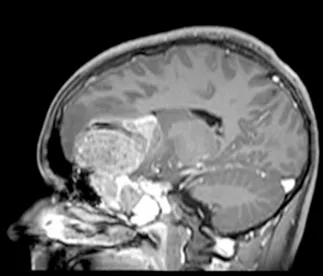

脑部和鼻旁窦计算机断层扫描(CT)和磁共振成像(MRI)扫描显示右侧存在5.5×4.4×5.6厘米肿块,起源于鼻腔、筛窦和蝶窦区域。肿块已侵蚀筛板进入前颅窝。该肿块在CT扫描上未出现钙化(图1),与脑组织等密度,伴有不均匀对比增强。肿块在T1和T2加权MR图像上(图2、3、4)与脑组织等信号,钆增强后显示不均匀强化。注意到周围存在血管源性脑水肿和占位效应。脊柱MRI未见转移证据。

图3:矢状位T1加权钆增强MRI扫描,显示肿瘤团块从鼻旁窦侵蚀进入前颅窝。